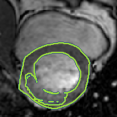

4.2 Visual assessment

We select the case that achieves the highest and lowest dice score for visual assessment. Fig. 4 shows example segmentation results where the proposed method achieved the highest agreement with the ground truth delineations. Fig. 5 shows example segmentation results where the proposed method achieved the lowest agreement with the ground truth delineations.

| (a) LV BG | (b) RV BG | (c) LV NM | (d) LV ME | (e) LV MS |